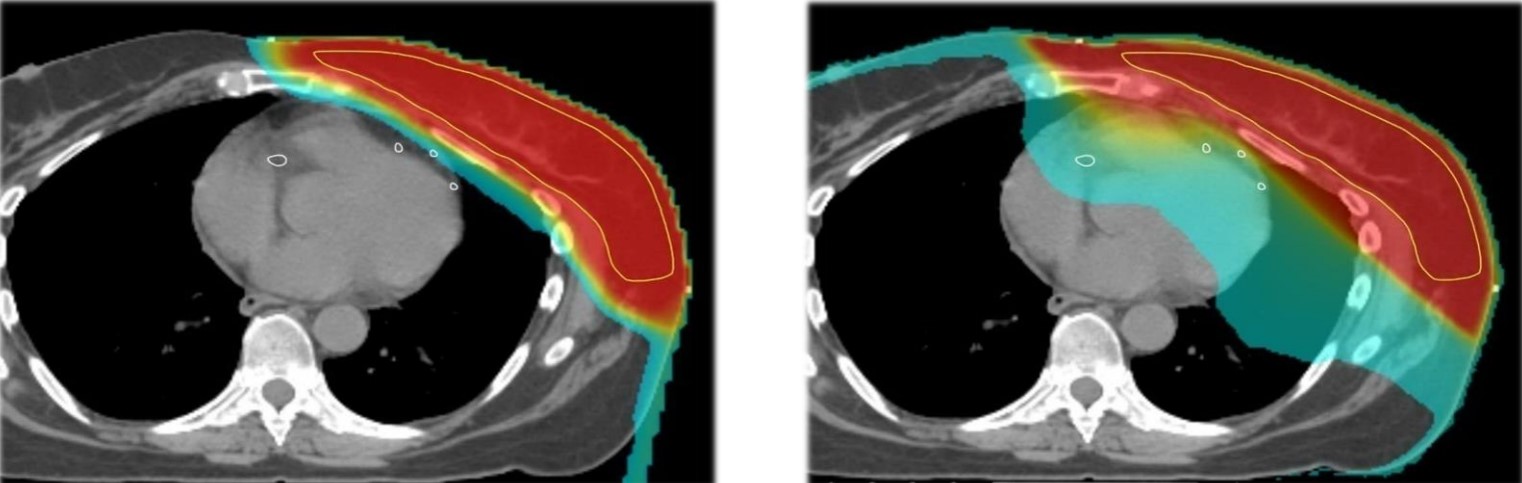

據(jù)《胃腸腫瘤學(xué)》雜志刊登的一篇關(guān)于各項(xiàng)放療技術(shù)治療食管癌患者的劑量?jī)?yōu)勢(shì)的文章顯示,與3D適形放療(3DCRT)相比,IMRT改善了器官的劑量分布;治療計(jì)劃和劑量學(xué)的比較研究進(jìn)一步顯示,與3DCRT和IMRT相比,質(zhì)子治療可顯著降低心臟和肺的照射劑量。質(zhì)子治療可最大程度地保護(hù)心臟前部組織,減少心臟的照射劑量,具有明顯的臨床優(yōu)勢(shì)。

與調(diào)強(qiáng)放射療法相比,質(zhì)子治療可以進(jìn)一步保護(hù)正常器官免受照射,顯著減少總輻射劑量,降低晚期毒性反應(yīng)及繼發(fā)性惡性腫瘤的發(fā)生風(fēng)險(xiǎn)。

在意大利APSS質(zhì)子中心一項(xiàng)回顧性分析納入13例胃癌患者,其中對(duì)調(diào)強(qiáng)放射療法(每日6個(gè)照射野)和雙被動(dòng)散射/均勻掃描質(zhì)子治療(每日2~3個(gè)照射野)進(jìn)行比較,其中所有患者均接受劑量為45~54 Gy的輔助治療。

結(jié)果顯示,質(zhì)子治療顯著減少了小腸、肝臟、左/右側(cè)腎臟和心臟的低-中劑量區(qū),靶區(qū)外的總照射劑量也顯著降低。13例患者中有4例患者接受了質(zhì)子治療,掃描結(jié)果顯示質(zhì)子治療掃描的穩(wěn)固目標(biāo)體積覆蓋范圍在±2%之內(nèi)。